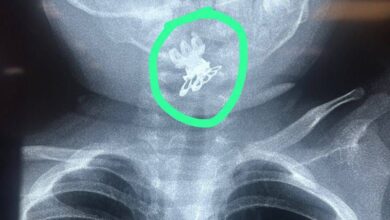

مستشفى الصدر في النجف ينجح بإنقاذ طفلة بعمر سنة ونصف ابتلعت قرّاصة شعر

تمكن فريق طبي بمدينة الصدر الطبية في النجف الأشرف من إنقاذ حياة طفلة تبلغ من العمر سنة ونصف، بعد تعرضها…